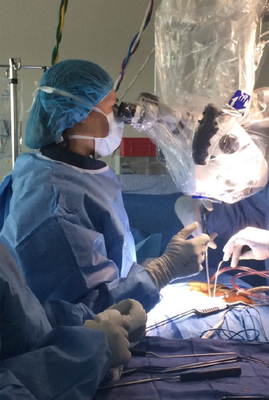

Led by UCSF fellowship-trained Dr. Carrer, we provide board-certified expertise for complex spine conditions and acute injuries.

At the Comprehensive Orthopaedic & Spine Institute, our objective is simple: to provide a practice where patients can access the full gamut of musculoskeletal treatments under one roof. Whether you are suffering from acute sports injuries, overuse conditions, occupational injuries, or high-energy trauma from motor vehicle accidents, we are here to guide you back to health.

- Extensive Surgical Experience with both minimally invasive and complex reconstructive procedures

Dr. Carrer leads a multidisciplinary team that provides access to the full gamut of musculoskeletal treatments, from acute sports injuries and occupational trauma to complex spine surgery. Our unique holistic approach integrates traditional medicine with alternative therapies, connecting you with a network of physiatrists, pain management specialists, chiropractors, and nutritionists all working in unison to optimize your health. Whether you are recovering from a motor vehicle accident or seeking relief from chronic overuse conditions, our goal is to empower you through education, innovation, and compassionate, personalized care.